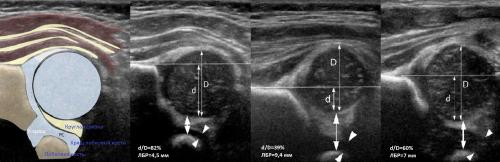

У 35 (4,81%) детей выявлена простая двусторонняя дисплазия тазобедренных суставов, без пространственных нарушений (рис. 2). В результате данной патологии происходит задержка сроков оссификации (формирования ядра), которая связана с пониженным содержанием кальция в организме ребенка (впоследствии при увеличении физической нагрузки на суставы, когда ребенок после 6 мес начинает сидеть и стоять, может произойти деформация головки бедренной кости).

Рис. 2. Простая дисплазия - задержка сроков оссификации без пространственных нарушений (ребенок 5 мес).

Тип 2а тазобедренных суставов (рис. 3) диагностирован у 46 (11,6%) детей. Это вариант физиологической задержки развития тазобедренных суставов у детей в возрасте до 12 нед, при котором угол α меньше 59°, но больше 50°, соответственно угол β больше 60°.

Тип 2б тазобедренных суставов выявлен у 25 (6,33%) детей - дисплазия тазобедренных суставов у детей старше 3 мес (рис. 4). Костная вертлужная впадина недостаточно развита, костный эркер закруглен, костнохрящевое соотношение меньше 2/3, хрящевая часть крыши охватывает головку бедренной кости. Угол α меньше 59°, но больше 50°, угол β больше 60°.

Тип 2с тазобедренных суставов (рис. 5) обнаружен у 2 (0,51%) детей. Это вариант тяжелой дисплазии в любом возрасте. Все составляющие сустава недоразвиты. Костная часть вертлужной впадины уплощена, костный эркер закруглен или плоский, хрящевая часть вертлужной впадины расширена, но еще охватывает головку бедра. Угол α меньше 49°, но больше 43°, угол β больше 65°, но меньше 72°. Такой тип суставов без соответствующего лечения, влечет прогрессирующее децентрирование головки бедра.

На первом этапе тазобедренный сустав сканируют в продольной плоскости. Проводят основные линии, измеряют костное покрытие головки, расстояние от лобковой кости до головки, ∠α и ∠β, а также определяют тип строения по Графу.

Проведите базовую линию по наружному контуру подвздошной кости и обозначьте головку бедренной кости, аппарат автоматически вычисляет степень костного покрытия головки. Костное покрытие головки в случаях предвывиха 40-50%, подвывиха

Линии костной (красная) и хрящевой (зеленая) крыши проходят через костный выступ, а так же начало Y-хряща и центр гиперэхогенного кончика суставной губы, соответственно. Степень развития костной крыши определяет ∠α, а хрящевой крыши ∠β.